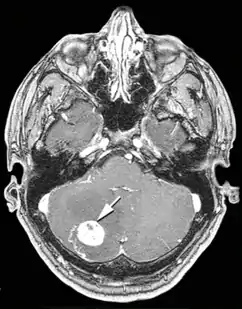

Гемангіобластоми головного мозку

Вузол гемангіобластоми складається з клубка тонкостінних судин. При введенні в кров контрастних речовин пухлина накопичує введені препарати, завдяки чому добре контрастується на ангіограмах, комп'ютерних та магнітно-резонансних томограмах. Визначаються великі патологічні артерії і вени, можуть виявлятися артеріо-венозні шунти. При проведенні комп'ютерної (КТ) та магнітно-резонансної (МРТ) томографії діагностуються дві форми пухлини — вузол з або без кістозного компонента. Перша форма характеризується тим, що великі кісти виконують велику частину об'ємного утворення. Вузол може взагалі не визначатися з допомогою нейровізуалізаційних методів дослідження.

Кіста гемангіобластом зазвичай округлої або овальної форми, на комп'ютерній томографії має низьку щільність (8-14 одиниць Хаунсфілда). При введенні контрастних речовин щільність її вмісту і стінок не змінюється. Вузол пухлини визначається на КТ у вигляді вогнища підвищеної щільності, частіше негомогенной зернистої структури. Розташовується на одній зі стінок кісти, вдаючись у її просвіт, добре накопичує контрастну речовину.

При кістозній формі пухлини на магнітно-резонансних томограмах добре визначається кістозний компонент, який характеризується низькою інтенсивністю сигналу на Т1 - і високим сигналом на Т2-зважених томограмах. На цьому тлі добре візуалізується пристеночно розташований солідний вузол гемангіобластоми, котрий добре накопичує контрастну речовину.

При солідній формі гемангіобластоми в стромі новоутворення відзначається наявність округлих і звивистих ділянок втрати сигналу за рахунок кровотоку у великих судинах пухлини.